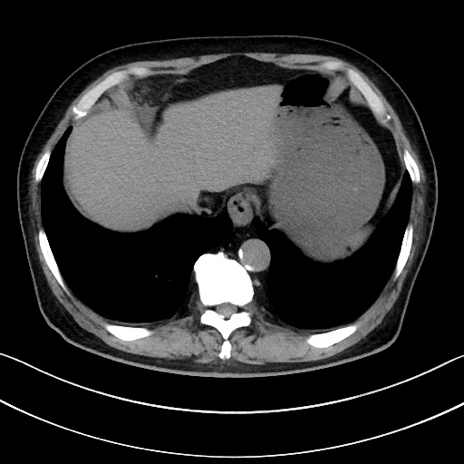

冠状断像

【症例】70歳代男性

【主訴】腹痛

【現病歴】今朝から腹痛あり。全体的に痛い。特に左上の方。排ガスが今日はない。冷や汗が出る。

【既往歴】直腸癌術後

【身体所見】左側腹部〜上腹部に圧痛あり。腹膜刺激症状明らかなではない。軽度反跳痛。左下腹部に術後瘢痕あり。

【データ】WBC 7700、CRP 0.02